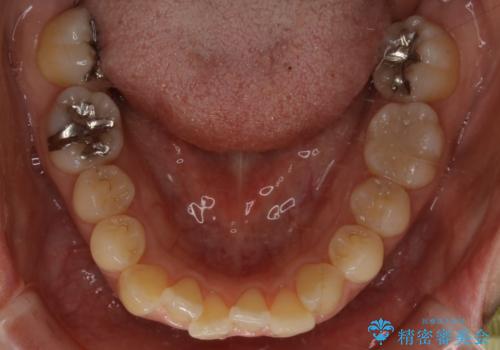

- 右上の2番目の歯が内側に入っているのと、下の前歯のがたつきが気になるとご相談にいらした方です。

上下左右の歯を後ろに動かして歯を並べるスペースを確保し、内側に入っていた歯を綺麗に並べ、前歯の中心もお顔の中心に合うようにしました。

矯正用アンカースクリューを埋入し、上下左右の歯を後ろに動かすことで歯を並べるスペースを作りました。

元々内側に倒れていた右下の奥歯は、ゴムかけを追加で行っていただくことによりしっかり起こすことが出来ました。